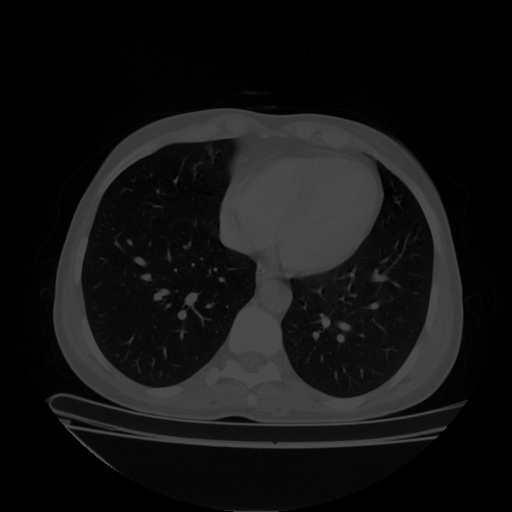

Generated VENOUS CT scan (A→B translation)

No window - Raw intensity values

Lung window (WL -600, WW 1500 β†’ Low βˆ’1350, High +150)

Mediastinum window (WL 40, WW 400 β†’ Low βˆ’160, High +240)